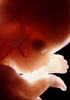

Carnegie Stage 23 (56 post-ovulatory days)

Most embryos at stage 23 are approximately 56-57 postovulatory days old and measure 23-32 mm in length. Distinguishing criteria for this stage include fusion of the eyelids at the medial and lateral margins, clear distinction of the subdivisions of the upper and lower limbs, the forearms appear at or above the level of the shoulders, the superficial vascular plexus of the head is very close to the vertex, and the external genitalia are well developed but not always sufficiently to distinguish the embryo's sex.

(NOTE: These specimens are late stage 23.)